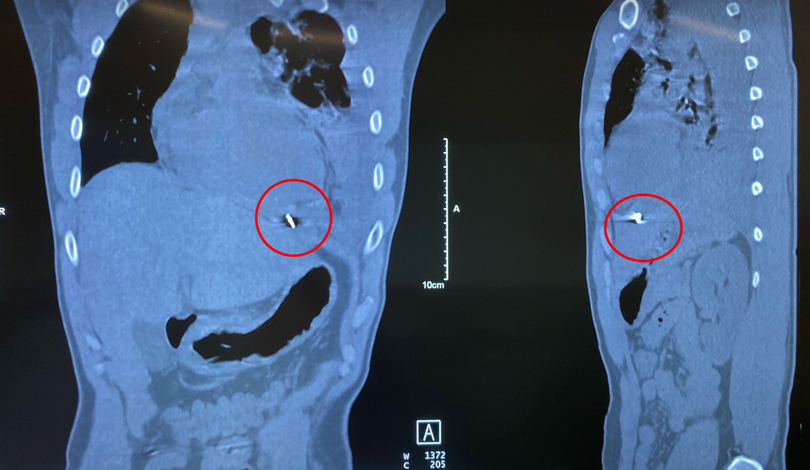

![]() |

| Hình ảnh dị vật găm trong ngực trái bệnh nhân (Ảnh - BVCC) |

Ngay lập tức, các bác sĩ đã cho bệnh nhân thở oxy, theo dõi sát tình trạng hô hấp, đồng thời, khảo sát bằng siêu âm và chụp CT lồng ngực. Qua khảo sát, các bác sĩ phát hiện bệnh nhân bị tràn máu màng phổi trái mức độ nhiều, kèm theo xẹp phổi trái thụ động, có mảnh kim khí nằm trong cơ hoành, mặt dưới tâm thất trái.

Các bác sĩ đã tiến hành phẫu thuật mở ngực đường bên vào khoang màng phổi trái và màng tim của bệnh nhân có gần 1500ml máu và máu đông và tìm ra dị vật là 1 mảnh kim khí dài khoảng 1cm có cạnh sắc, làm rách mặt trước màng tim và găm vào mặt hoành của màng tim.